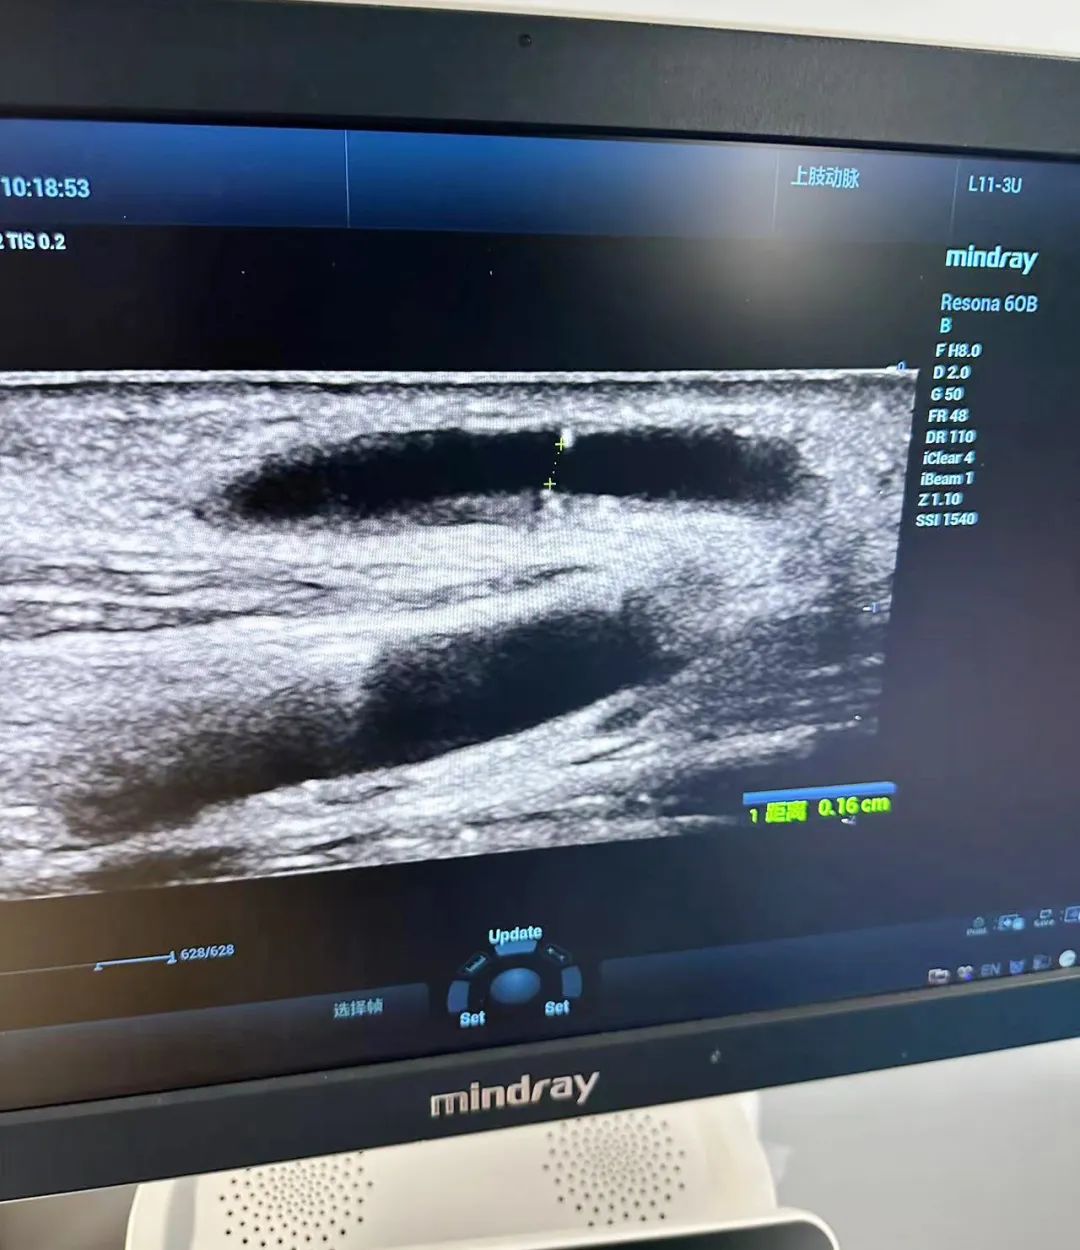

12日上午,在我院四樓遠程會診中心,李月紅教授與血透中心醫(yī)護人員共同開展一場腎友交流會活動。通過與腎病患者面對面的交流,她們更深入地了解了患者的實際需求和困擾,并就血管通路、腎性貧血、高磷血癥、血液灌流、飲食等方面提出了個性化的治療建議和指導(dǎo)。此外,李教授強調(diào),血管通路是透析患者的“生命線”。超聲對血管的評估、通路的建立、通路的管理方面發(fā)揮著重要作用。

交流會結(jié)束后,血透中心與彩超室通力合作,為多名血透患者進行了血管B超檢查。通過篩查,發(fā)現(xiàn)了一些患者血管通路出現(xiàn)問題,并及時指導(dǎo)他們進行血管通路干預(yù),以避免內(nèi)瘺的風(fēng)險。同時,李教授對內(nèi)瘺評估及血流量測量,內(nèi)瘺穿刺等內(nèi)容進行細致講解,這一舉措有效提高了醫(yī)生對動靜內(nèi)瘺評估的能力,提升了護士動靜脈內(nèi)瘺彩超穿刺技術(shù)的水平,得到了醫(yī)患雙方的一致好評。